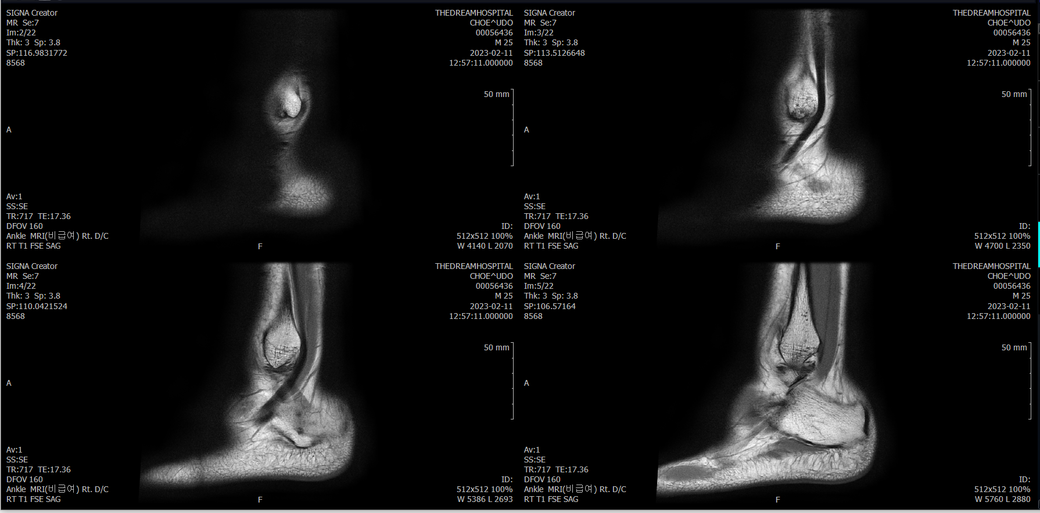

오른발목 mri 전체사진입니다. 제가 병원을 갈수없는상황인지라.... 봐주시면 감사하겠습니다.

엑스레이에서는 문제가 없다고 하여 오른발목 mri촬영했습니다.